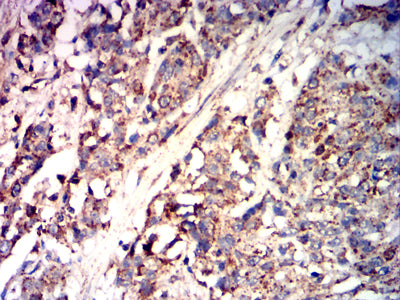

Immunohistochemical analysis of paraffin-embedded human esophageal cancer tissues using CD85K mouse mAb with DAB staining.